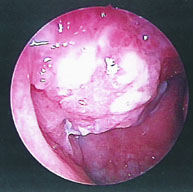

我們耳鼻喉科常接到其它科醫師因頸部切片後轉診要進行局部檢查的病患 (圖1),一看就發現在鼻咽部 (圖2)有明顯的腫瘤,以內視鏡鼻咽部切片證實為鼻咽癌,類似這種鼻咽癌的患者是不需要進行頸部腫塊的切片手術。所以無論如何,只要有頸部的腫塊應該馬上由專業的耳鼻喉科醫師進行詳細的頭頸部局部檢查,不宜冒然的進行頸部腫塊的切片。

圖1. 病患李先生接受頸部切片後轉診到耳鼻喉科進行局部檢查

圖2. 李先生在鼻咽部有明顯的腫瘤,鼻咽部切片證實為鼻咽癌